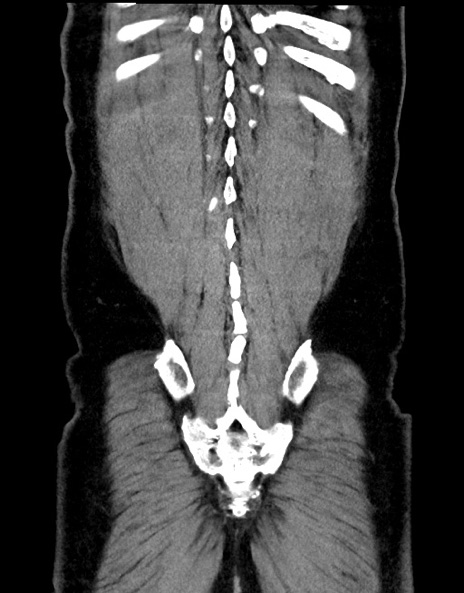

症例15(冠状断像)

【症例】70歳代男性

【主訴】腹痛

【現病歴】今朝から腹痛あり。全体的に痛い。特に左上の方。排ガスが今日はない。冷や汗が出る。

【既往歴】直腸癌術後

【身体所見】左側腹部〜上腹部に圧痛あり。腹膜刺激症状明らかなではない。軽度反跳痛。左下腹部に術後瘢痕あり。

【データ】WBC 7700、CRP 0.02